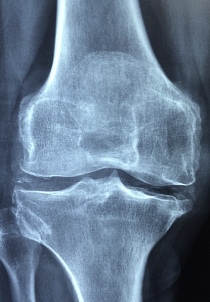

콘드로이친은 연골 손상이나 연골염 등으로 인한 관절통을 완화하는 데 도움이 되는 성분입니다. 이 성분은 연골 조직의 구성성분 중 하나인 그리코사민을 생성하기 위해 필요한 원료로 작용하며, 연골 세포의 생산성을 높여 염증을 줄이고 뼈 건강에도 좋은 영향을 줍니다. 또한, 콘드로이친은 스포츠 재활 프로그램에서도 사용되며, 관절염이나 골다공증 등의 질환 예방에도 도움이 됩니다. 연구에 따르면 콘드로이친은 통증 완화와 함께 기능적 측면에서도 이점을 제공하며, 오랜 기간 안전하게 복용될 수 있습니다. 하지만 콘드로이친은 항응고제와 상호작용하므로, 항응고제를 복용하는 환자들은 의사와 상의한 후 복용해야 합니다.